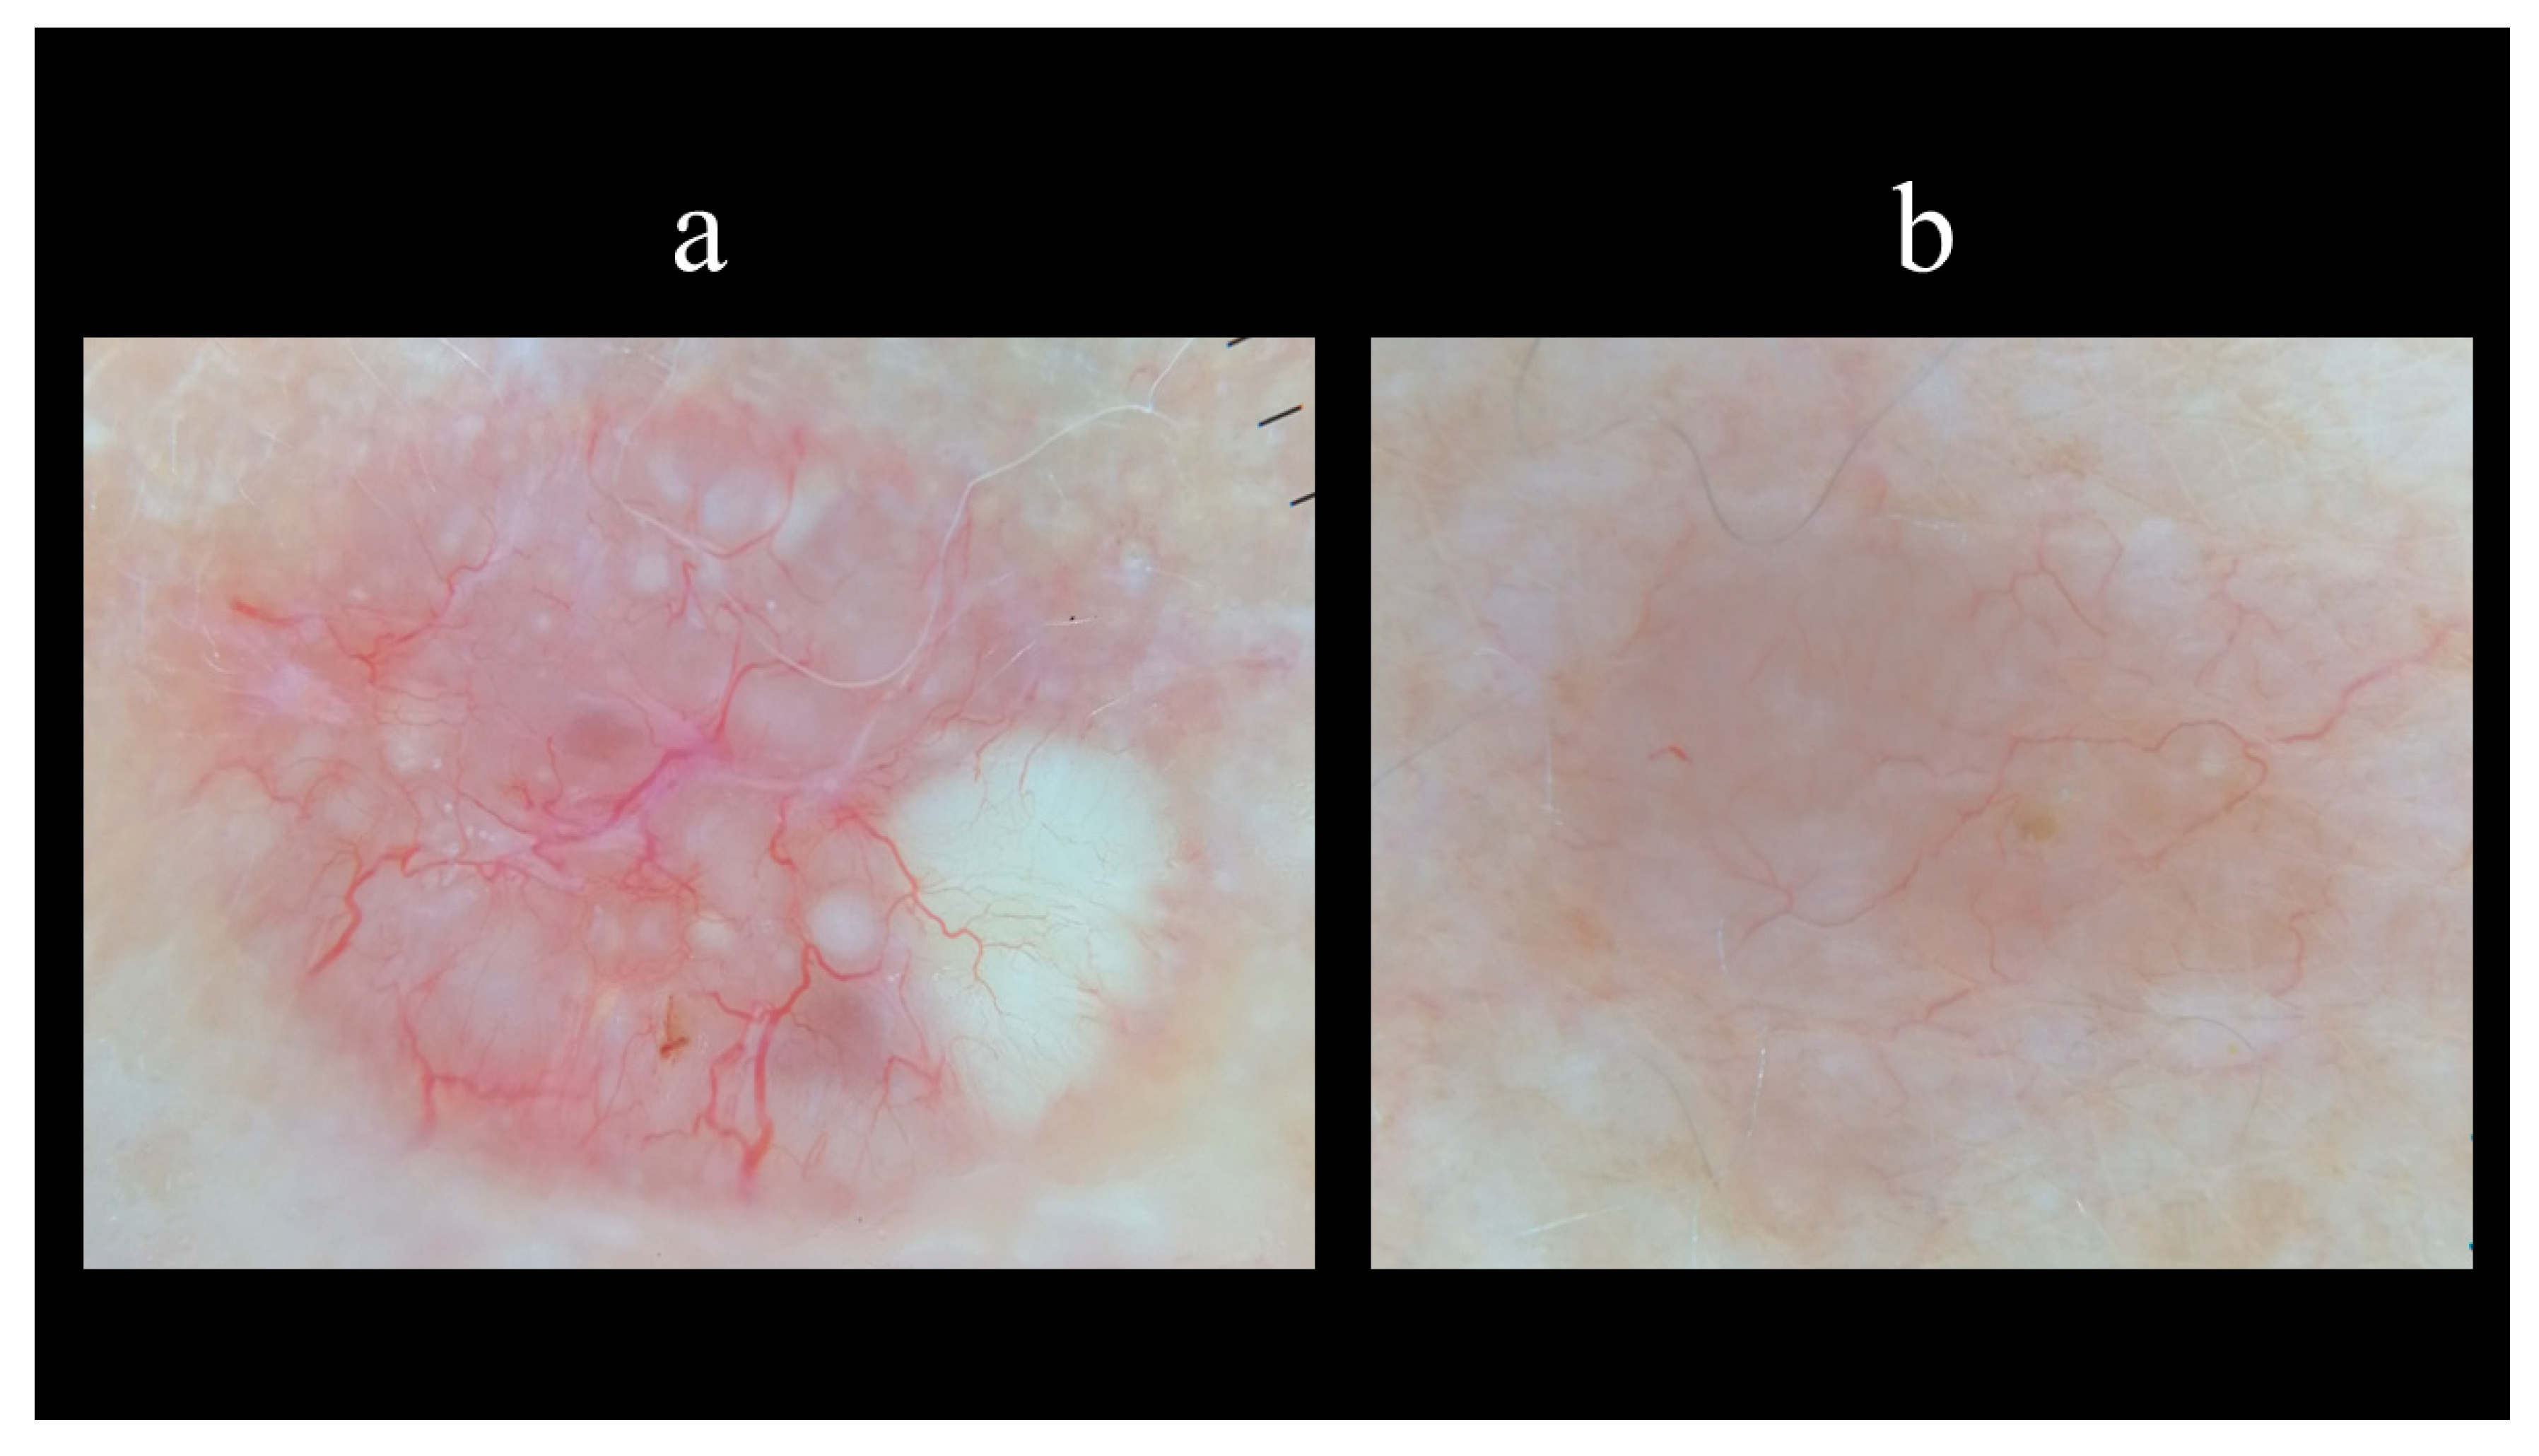

5. Dermoscopy